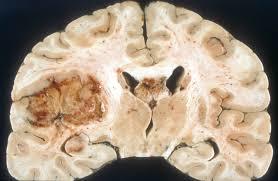

What does it look like grossly?

flattened, widened gyri with narrowed sulci

Flattened gyri/narrow sulci with compressed ventricles and soft brain

(picture is glioblastoma with vasogenic edema)

Explain how a brain tumor like glioblastoma results in vasogenic edema

Have extensive angiogenesis w/ microvascular proliferation, poorly formed BBB

end up with extensive vasogenic edema and mass effect